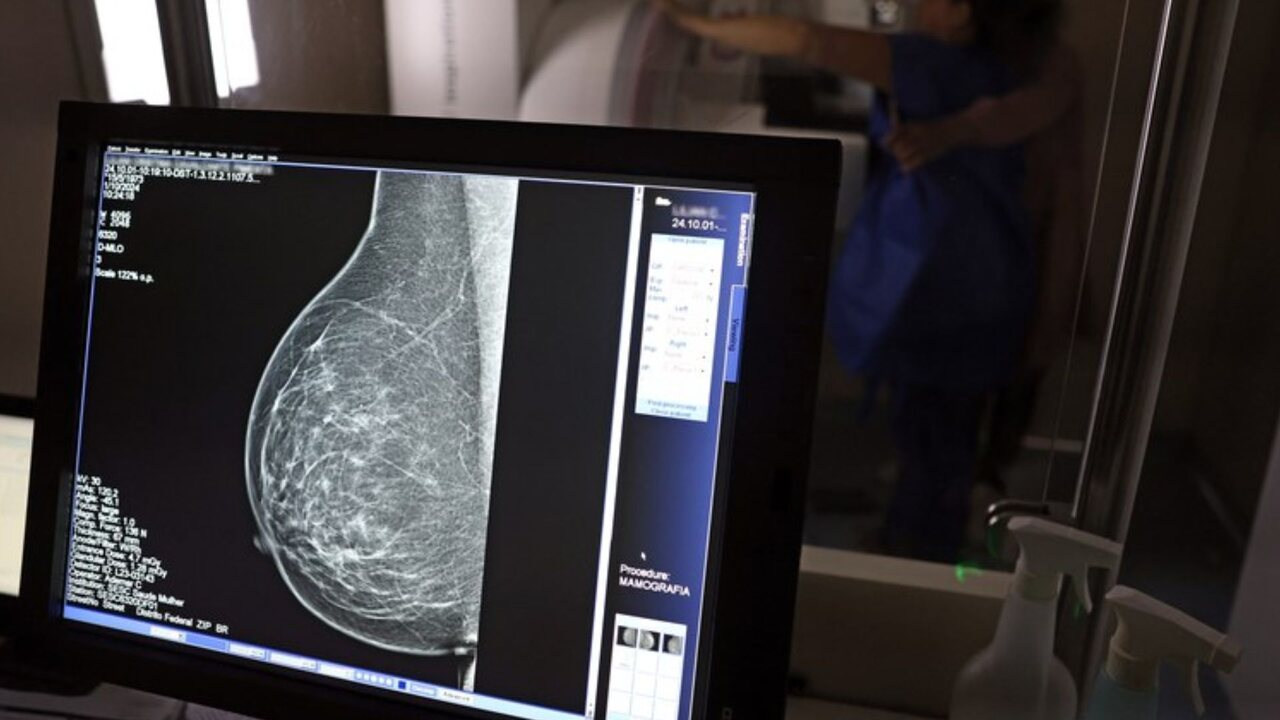

Entre os tipos de câncer, o de mama é a principal causa de morte em mulheres no Brasil

Um projeto de lei que obriga o exame de câncer de mama em mulheres com mais de 40 anos avançou na Câmara de Jaraguari e pode virar lei. Assim, a mamografia — um dos mecanismos para a prevenção e o diagnóstico precoce da neoplasia mamária — pode virar exigência na cidade do interior de Mato Grosso do Sul.

O Ministério da Saúde garante o acesso à mamografia no SUS a mulheres de 40 a 49 anos, mesmo sem sinais ou sintomas de câncer. Conforme o Governo Federal, essa faixa etária concentra 23% dos casos da doença e a detecção precoce aumenta as chances de cura.

Segundo o último censo do IBGE (Instituto Brasileiro de Geografia e Estatística), Jaraguari possui 7.139 moradores. Desse número, 3.367 são mulheres — e, delas, 1.685 têm 40 anos ou mais. Entre os tipos de câncer, o de mama é a principal causa de morte em mulheres no Brasil.